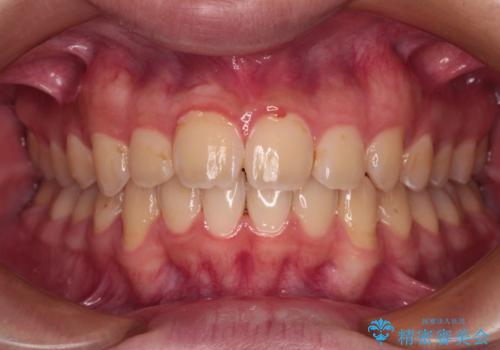

インビザラインで難儀する部分をワイヤー装置にて確実に改善しておくことで、インビザラインのみで行うよりも治療期間を短縮するとともに、より理想的な歯列に近づけて仕上げることができました。